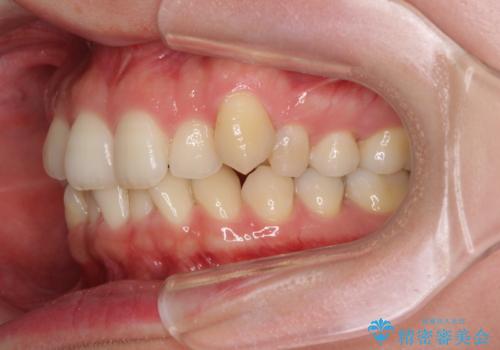

- 上下の前歯のデコボコを治したいとのことで来院された患者様です。

仕事柄、アジアの3つの国と地域を行き来するため、ワイヤー装置での治療は難しいと考えられました。

上下顎ともにIPR(歯と歯の間を削る)と歯列全体の拡大によって叢生が解消するように設計し、インビザラインにより治療を行うこととしました。